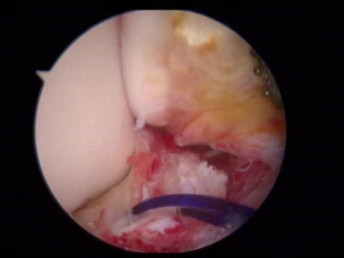

韌帶斷裂

修復(fù)斷裂的韌帶

醫(yī)生們?cè)谑中g(shù)中發(fā)現(xiàn),李先生的右踝關(guān)節(jié)軟骨損傷明顯,踝關(guān)節(jié)前方及內(nèi)外側(cè)均有不同程度的骨質(zhì)增生,相互撞擊引起疼痛,同時(shí)距腓前及跟腓韌帶斷裂。手術(shù)醫(yī)生利用磨鉆,小心翼翼將引起撞擊的骨刺一一去除,然后,修復(fù)了損傷的關(guān)節(jié)軟骨,最后,為他完成了距腓前和跟腓韌帶的修復(fù)。